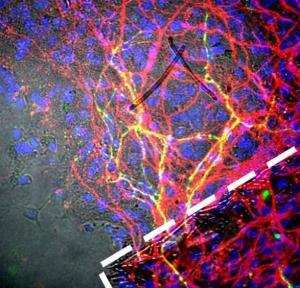

Son équipe a conçu un micro-échafaudage en 3D constitué de fibres polymères minuscules. Des centaines de neurones (en rouge) vont se fixent à ces fibres (en jaune) et se ramifier pour pouvoir envoyer leurs signaux. Chaque petit échafaudage (en blanc sur visuel ci-contre) mesure environ 100 micromètres de large soit, à peu de chose près, l’épaisseur d’un cheveu humain. Les chercheurs prennent » tout un tas » de ces fibres et les injectent, ici, dans le cerveau de souris.

Source: Nature Communications 17 March 2016 doi:10.1038/ncomms10862 Generation and transplantation of reprogrammed human neurons in the brain using 3D microtopographic scaffolds (Visuel@Crédit: Neal K. Bennett, Moghe Laboratory, Rutgers Biomedical Engineering)